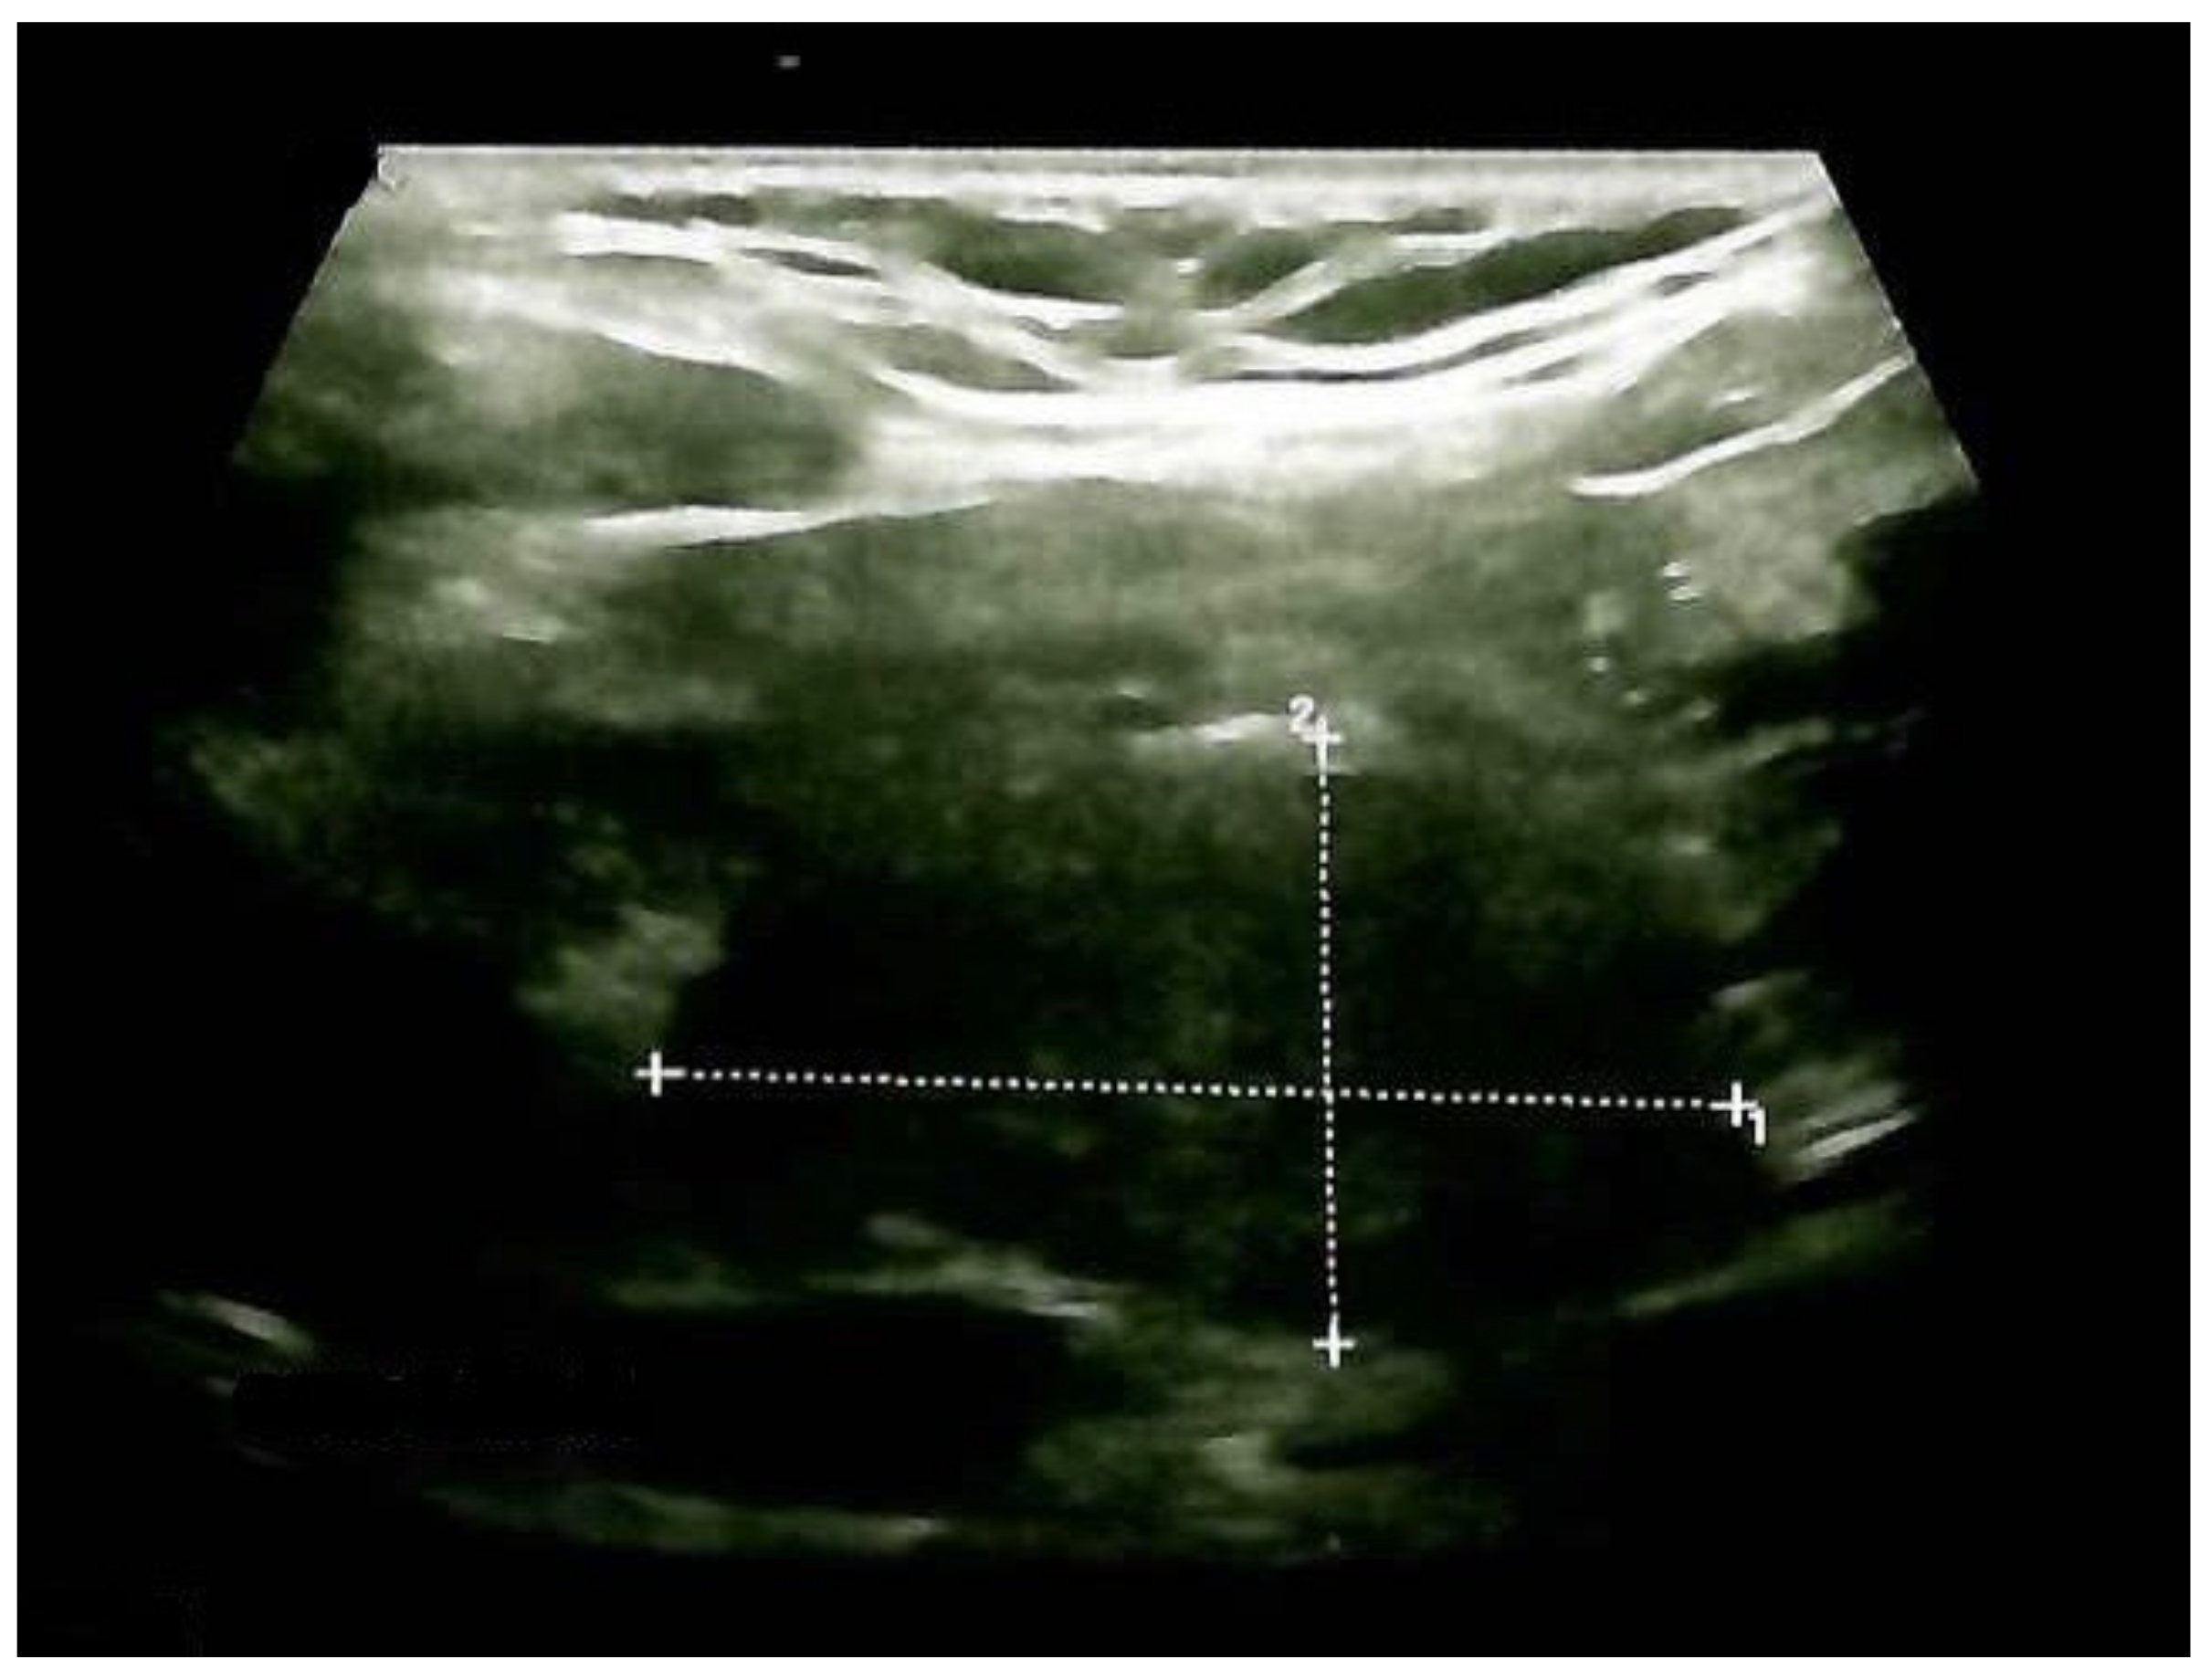

Thyroid ultrasound confirmed previous aspects in terms of gland enlargement and a multinodular goiter with a small increase in the largest nodule diameter. The right lobe was 2 by 2 by 4.3 cm, and the left lobe was 1.8 by 1.9 by 3.8 cm, with a hypoechoic, intensely inhomogeneous pattern; the lower half of the right thyroid lobe had a nodular conglomerate of 3.1 by 1.6 by 1.7 cm. Inferior to the right thyroid lobe, a hypoechoic mass with a structure similar to that of the thyroid of 3.66 by 2 by 2.6 cm was observed (ETTM). She had no neck lymph node involvement (Figure 5).

Figure 5.

Anterior neck ultrasound: hypoechoic mass (ETTM) extending from the right thyroid lobe, with a structure similar to the thyroid and pre-tracheal extension of 3.66 by 2 by 2.6 cm (longitudinal plane).

A neck ultrasound showed mild post-surgical cervical edema and no thyroid remnants (Figure 11).

Figure 11.

Anterior cervical ultrasonography after total thyroidectomy and ETTM removal: cervical edema and no thyroid tissue remnants.